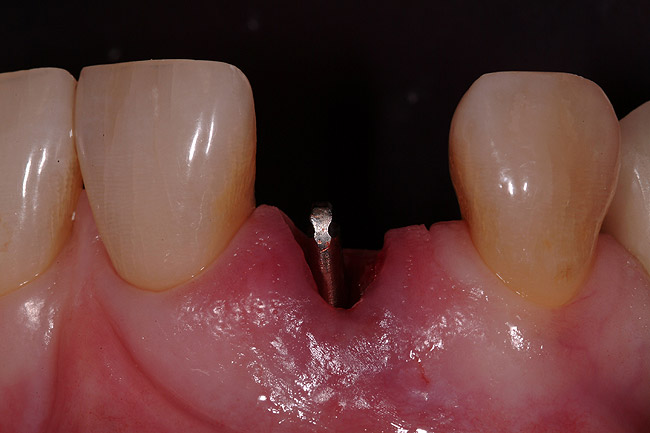

A 54-year-old, non-smoking woman presented with a root fracture at the maxillary right lateral incisor (Figure 1). The patient presented with a 10-mm pocket at the mid-facial probing depth, and a Grade 2 mobility. The preoperative peri-apical digital radiograph can be seen in Figure 2. A natural diastema existed on the distal aspect of the right maxillary incisor, and the patient did not wish to have this corrected. To hold the natural tissue emergence profiles throughout the treatment phase, the immediate implant placement and provisionalization procedure was chosen to treat the affected site. Before the procedure, an occlusal index and registration was taken so that when the retrofitting of the natural tooth shell was accomplished, the exact location of the natural tooth shell could be seated on the implant abutment at the time of implant placement (Figure 3). After administration of an appropriate local anesthetic, tooth No. 7 was removed by an atraumatic technique to preserve the natural soft tissue emergence profiles present pre-surgically (Figure 4). After tooth removal, debridement of the extraction socket was accomplished by curettage of the socket, followed by rotary instrumentation with a course #8 round diamond to ensure removal of all remnants of the periodontal ligament, granulation tissue, and localized debris. To aid in the debridement, the patient was started on a preoperative administration of Augmentin 875 mg, taken the day before treatment, and once again 1 hour before the surgical visit. The patient then continued this antibiotic course for a total of 10 days.

Figure 1  Pretreatment clinical view.

Figure 1